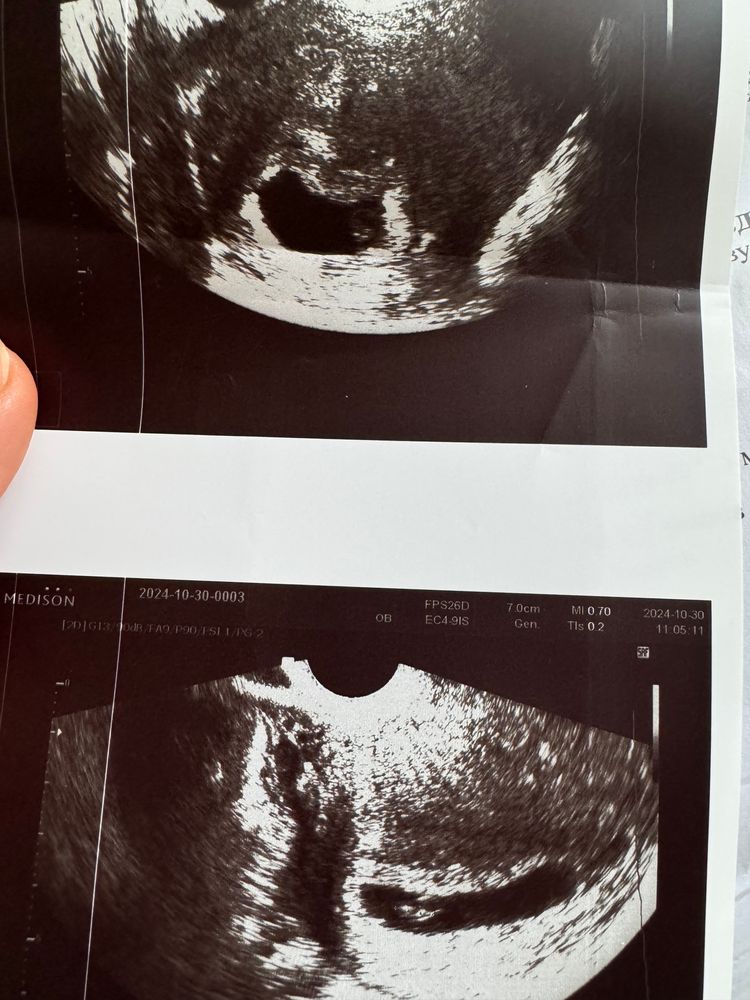

у меня от датчика всегда живот каменеет и яйцо сплющивает. Но еще зависит от проекции, с какой стороны врач смотрит. вот у меня 2 фото, но круглого нет. Сказала что все в норме, просто тонус от датчика. Изображение

Елена, вот как раз когда эту фоточку сделали)) было 6 недель 4 дня, ктр 7,5 мм чсс126 🙏